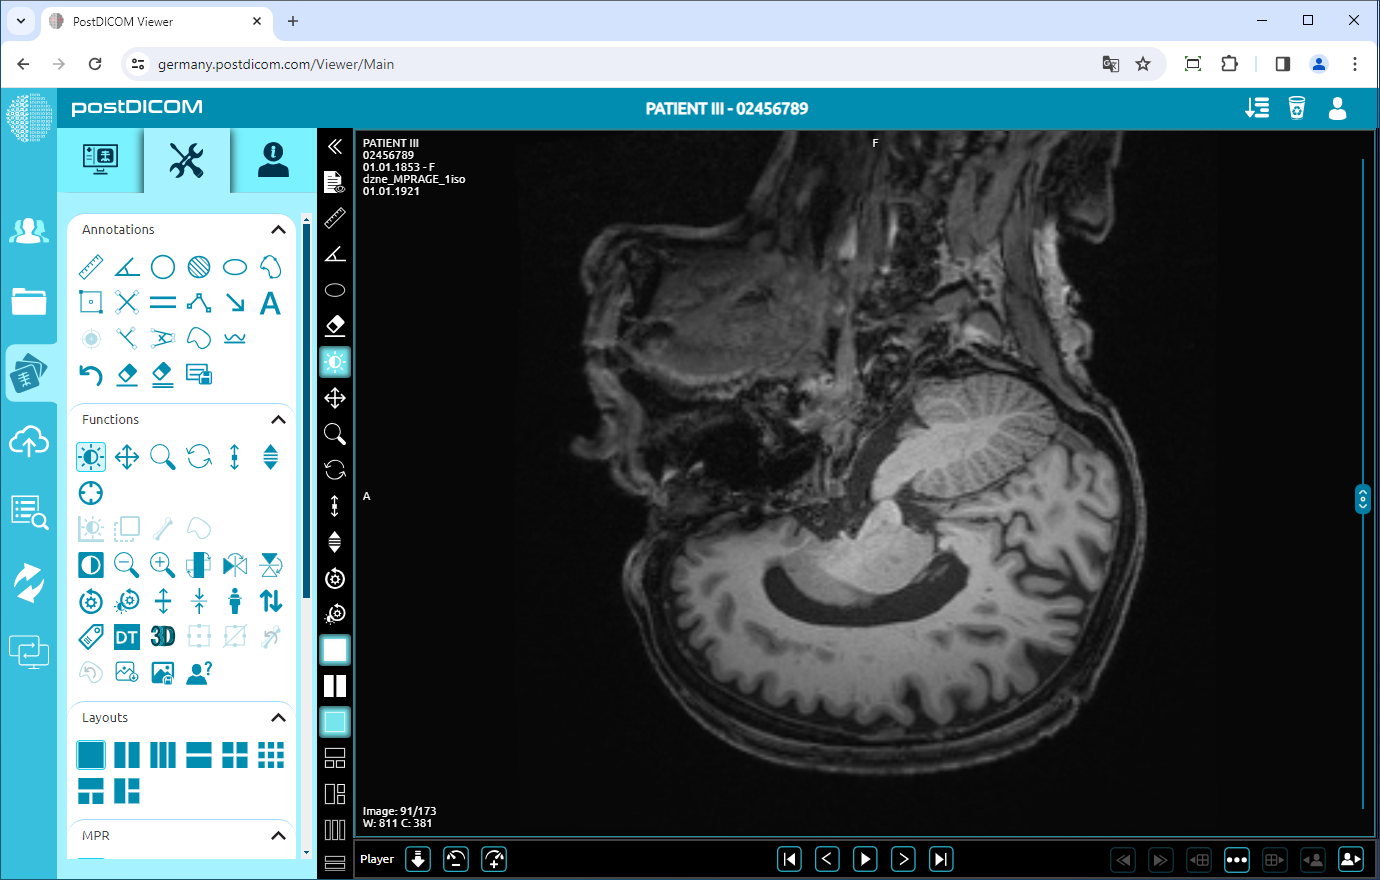

Flip Vertical

Click on the “Flip Vertical” icon on the left side of the page to flip the image vertically.

Once you have clicked, you will see the vertical mirror view of your image on the viewport.